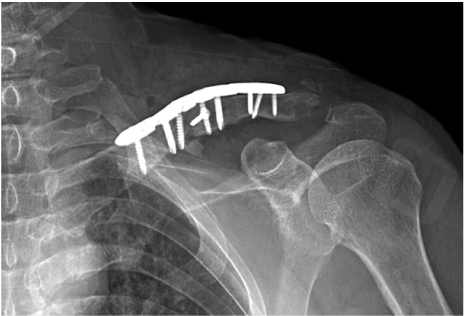

A 56-year-old, right-hand-dominant, male patient was transferred to our hospital for nonunion of mid-shaft clavicular fracture. The patient's first operation was performed at another hospital 5 months prior, where a plate and screws were implanted for repair (Fig. 1). His radiographs upon admission revealed loosening of the implant. On physical examination, he presented with left shoulder discomfort, tenderness along his fracture site of the left clavicle, and limited range of motion of the left shoulder secondary to pain. Neurovascular status was intact. When compared to radiographs obtained after the first operation, radiographs of the clavicle taken at admission demonstrated increased angulation of the fracture site with a visible fracture site gap and distal implant loosening (Fig. 1). He also had avascular necrosis of bilateral femoral heads. We performed a revisionary open reduction and internal fixation of the left clavicle with an autogenous cancellous bone graft from left femoral head after simultaneous left total hip arthroplasty. We recommended right total hip arthroplasty.

Fig. 1

Immediate postoperative left clavicle anteroposterior view after the first surgery.